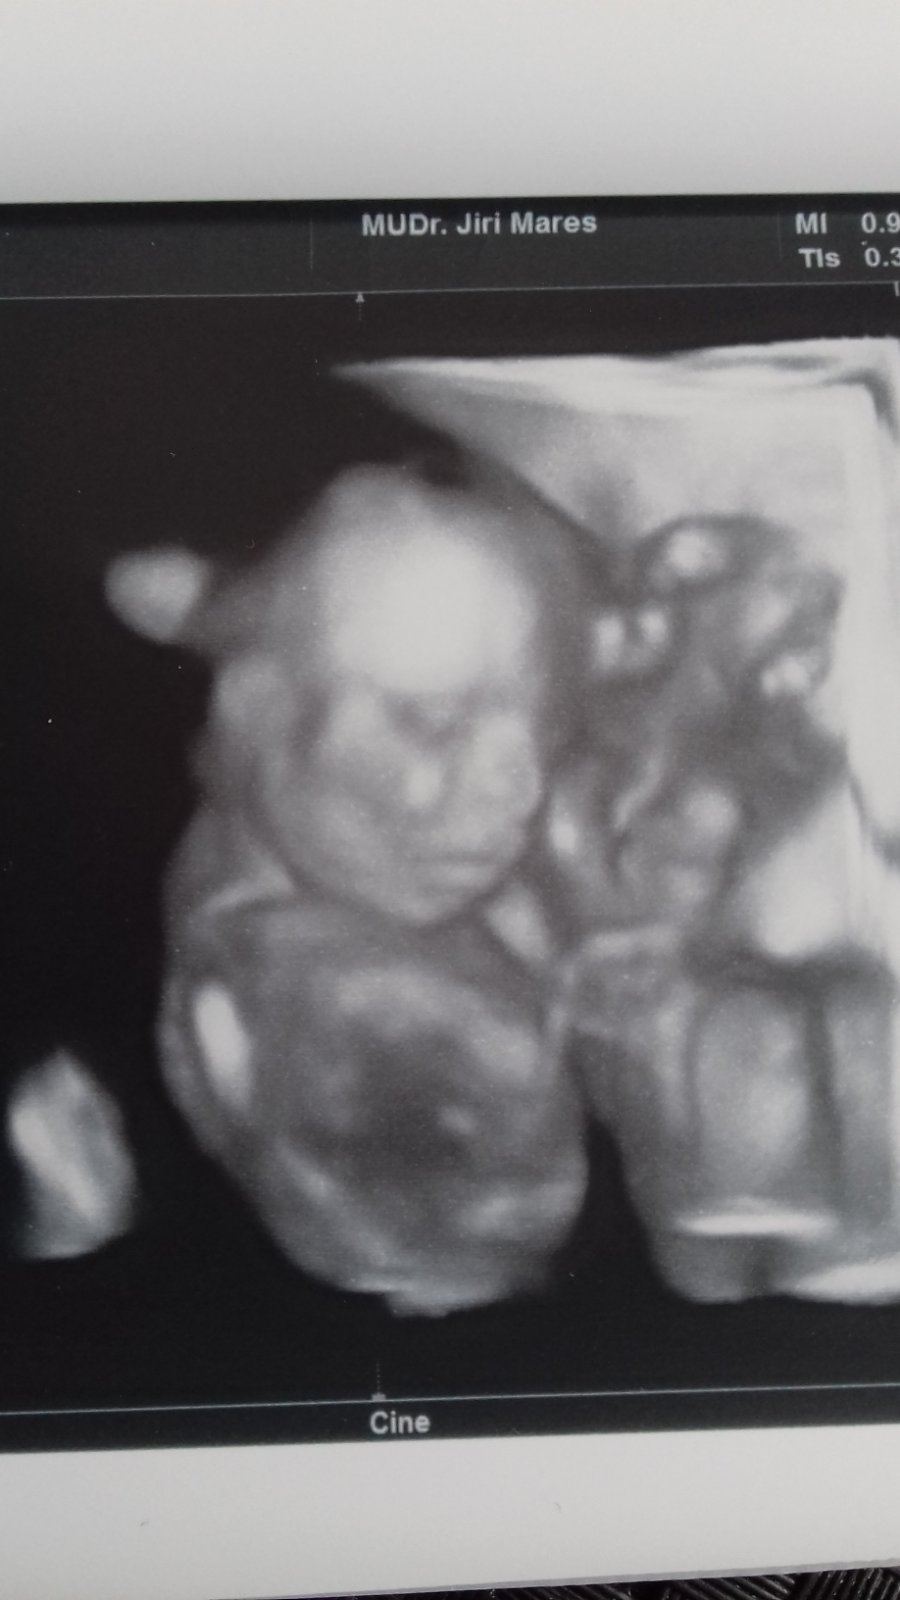

@pitrisek87 Zrovna dnes jsem mněla 3d sono ,orgány až tak kontrolovat nebudou spíš tvaričku prcka a pohlaví určíte, ja to mám u dr.tak že jedu celkem třikrát po 10-15 minut a pak udělá i video.

@dominika963852 jste kouzelný 😍taky jsem byla unesená..ty miminka je krásně vidět ...

Holky tak dnes mi dr.na tom 3d řekl ... s kluka je holka! Manžel to predychal a ted už se těší na princeznicku ☺Včera jsem mněla bolesti v podbřišku a tlaky tak mi dal magnezko doufám se to zlepší.

@michaelarei Tak to je krásná fotka!